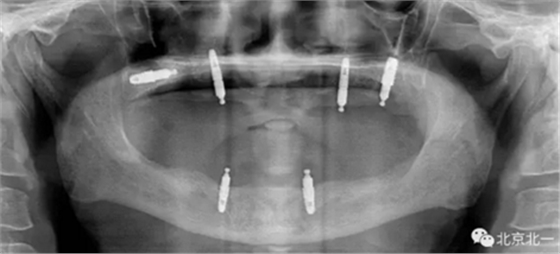

圖四:王明老師接手時植體往后移位,

圖五:北一種植王明老師出馬,采用外側(cè)壁開窗微創(chuàng)取出術(shù)。